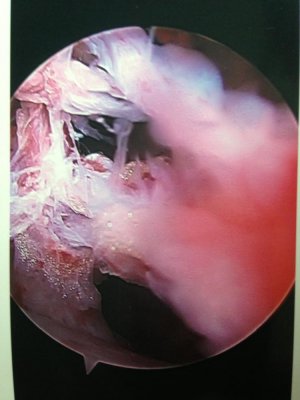

Here are a few pictures that the doc took while using the scope inside my shoulder.

He told me these were torn / frayed tendons and adhesions that were growing to lock my shoulder down in place. He was able to clean everything up and as soon as I finish healing I will be good to go.

I know it looks kind of gross, but I think it's totally amazing what they can do now with todays technology. Simply amazing.